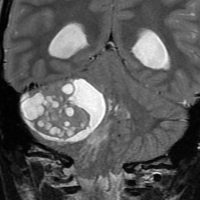

典型的な小脳虫部(小脳の真ん中)の髄芽腫です。横の方,ルシュカ孔へ伸びていないので上衣腫と区別できます。ガドリニウムという造影剤で白く写っています。

この例は,小脳半球にできたものです。のう胞(水たまり)を形成しています。髄芽腫の大きな特徴は,造影剤を入れないCT(左側)で腫瘍が少し白く見えることです(灰白質より高密度といいます)。細胞密度が高いので高密度になります。この例はclassic medulloblastomaですが,MIB-1は45%に達するもので,急激な腫瘍発育を示します。